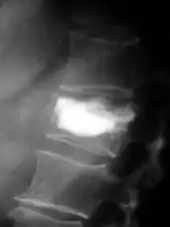

- Vues de fractures pathologiques

Fracture pathologique de l'humérus sur une métastase de carcinome du rein

Pour le diagnostic initial, la radio X classique a une importance centrale. L'indication pour des projections sur deux plans est toujours donnée en cas de soupçon de tumeur osseuse[87]. Les métastases ostéolytiques sont caractérisées par une perte de densité osseuse. Ceci se reconnaît sur la radio par un noircissement plus élevé, en raison de la plus grande transparence aux rayons X. Inversement, les métastases ostéocondensantes présentent à cause de la plus grande densité osseuse un noircissement inférieur. Les métastases ostéolytiques sur la colonne vertébrale sont nettement plus difficiles à reconnaître : seulement quand environ 50 % de la densité totale de l'os a disparu[87].